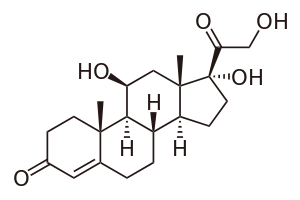

Cortisol

Cortisol is a steroid hormone, belonging to a broader class of steroids called glucocorticoids, produced by the adrenal gland and secreted during a stress response. Its primary function is to redistribute energy (glucose) to regions of the body that need it most (i.e., the brain and major muscles during a fight-or-flight situation). As a part of the body's fight-or-flight response, cortisol also acts to suppress the body's immune system.

Cortisol is synthesized from cholesterol in the adrenal cortex.[42] Its primary function is to increase blood sugar through gluconeogenesis, suppress the immune system and aid in fat and protein metabolism.[43]